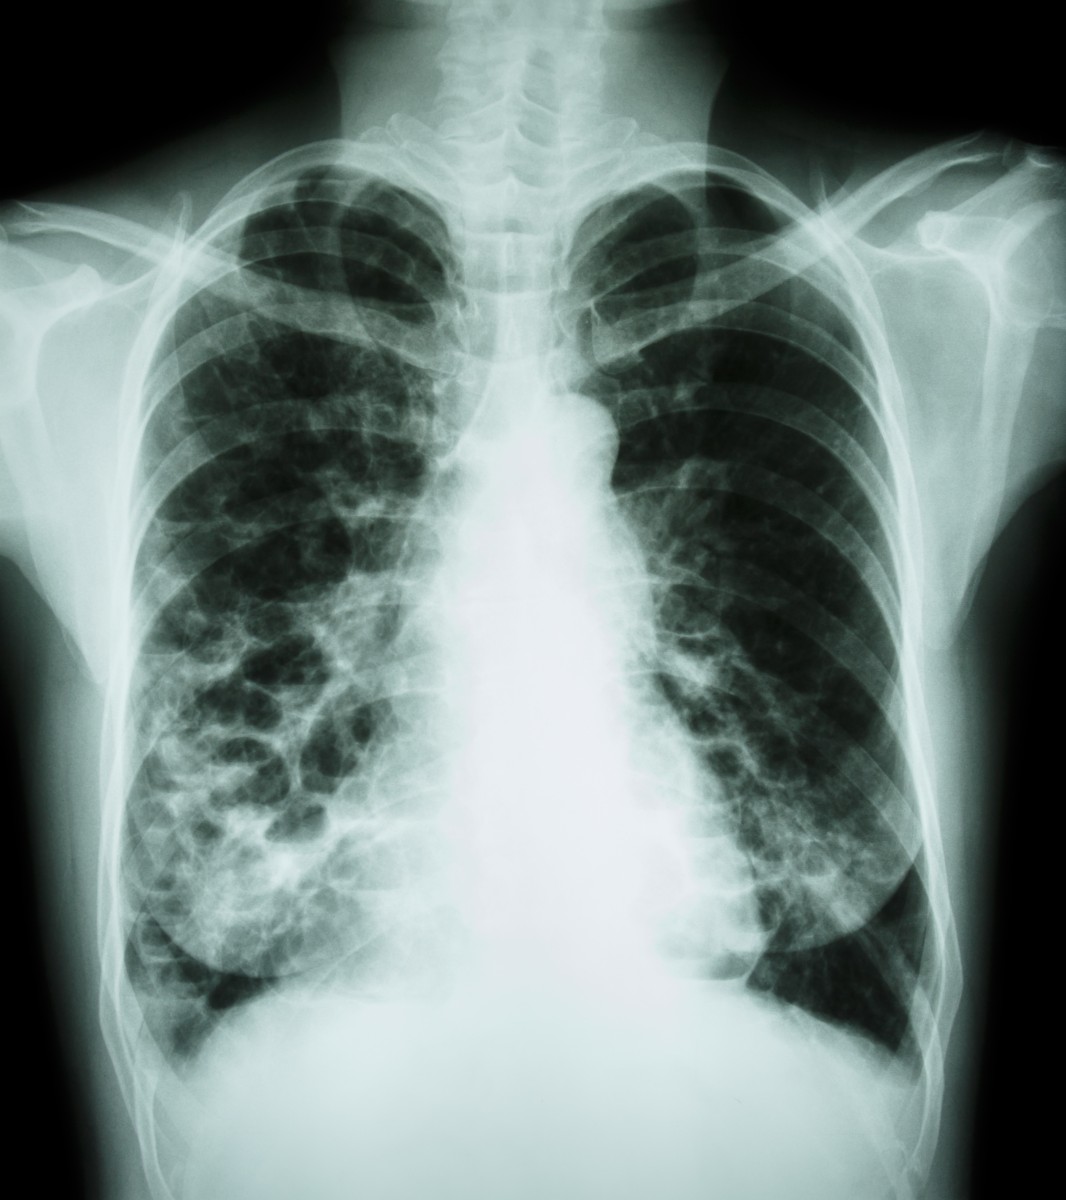

Chest x-ray revealing bilateral coarse reticulonodular opacities and …